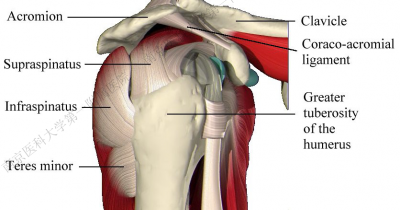

六、肩胛盂及韧带复合体损伤对肩关节后向稳定性的影响

1.肩胛盂后侧可以因骨折导致缺损(反Bankart损伤),或发生盂肱韧带附着处的撕脱骨折。

2.可能损伤的韧带复合体包括:

- 盂唇撕裂。

- SLAP损伤。

- 肩袖撕裂。

- 盂肱下韧带撕裂。

盂肱下韧带肱骨侧止点撕裂

八、治疗方法

胸大肌——三角肌间隙入路

九、外科技术要点

(一)充分显露肱骨头是治疗成功的先决条件:

- 以肱二头肌长头为标志切开肩袖,帮助显露肱骨头。

(二)切开肩胛下肌(是进一步显露肱骨头关节面的钥匙)